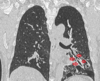

Estudios de imagen en COVID-19

Rx útil en seguimiento, poco sensible al inicio * Hallazgos similares a cualquier neumonía viral * Consolidación en vidrio despulido *Patrón reticular TC mayor sensibilidad + Consolidación periféricas en vidrio esmerilado

72

COVID-19 con patrón de vidrios despulido